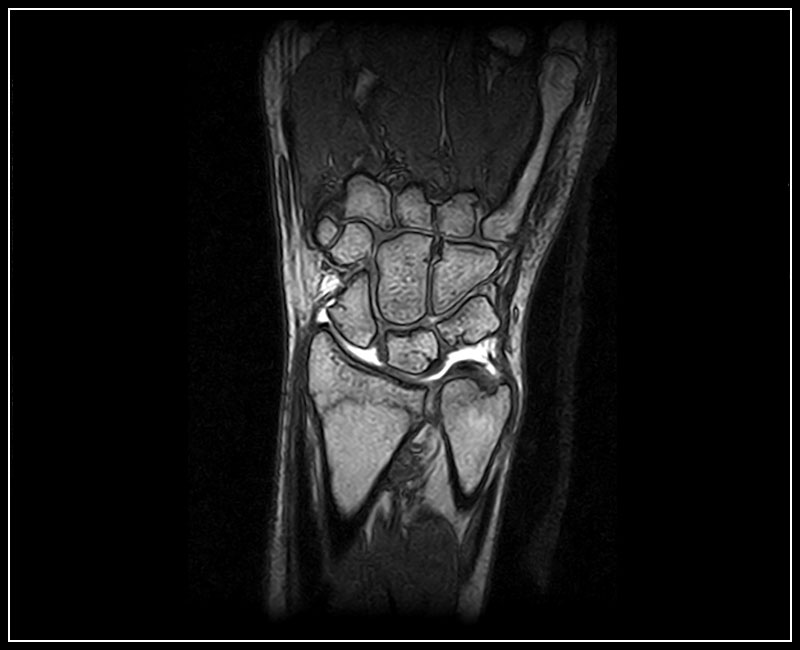

Klinické snímky